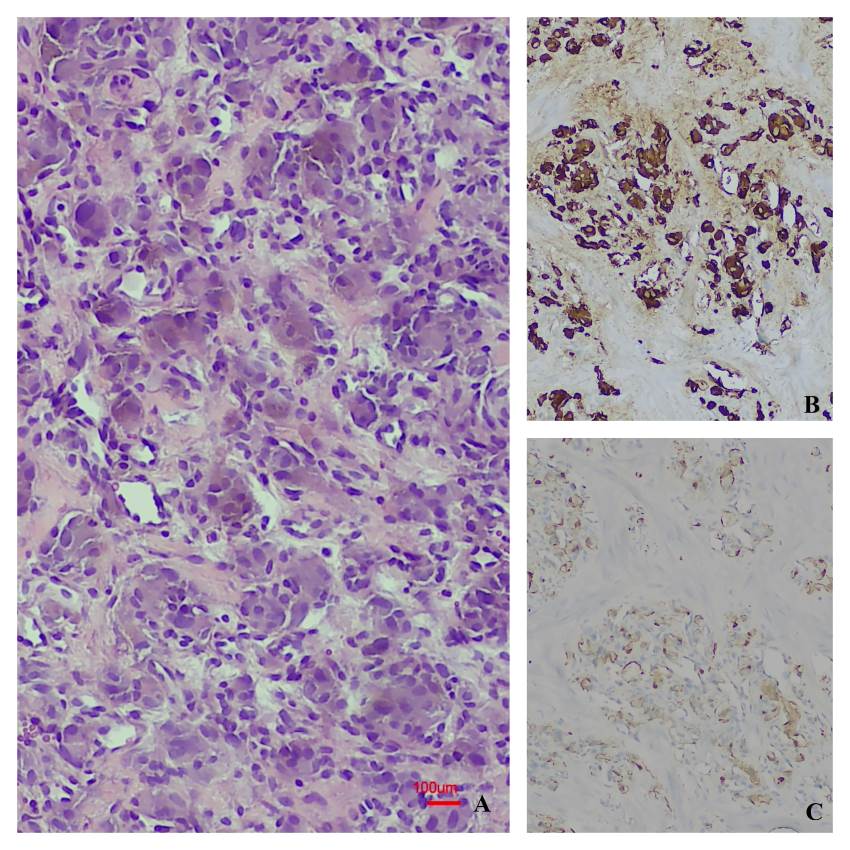

Results: During the specified period, a total of 20 patients were identified, most of whom were male. The kidney was the most frequently affected site. Malignant tumours were diagnosed in 11 patients, and benign tumours in 9. Leiomyosarcoma was the most common malignant tumour, while angiomyolipoma was the most frequently observed benign tumour. Other malignant tumours included rhabdomyosarcoma, liposarcoma, undifferentiated pleomorphic sarcoma, paraganglioma, malignant solitary fibrous tumour, and diffuse large B-cell lymphoma. Benign tumours included angioleiomyoma, schwannoma, renomedullary interstitial cell tumour, leiomyoma, and angiofibroma. Surgical procedures varied depending on tumour type and included excisional biopsy, partial resection, and radical resection. During the follow-up period (ranging from 1 to 38 months), survival was achieved in all patients with benign tumours, whereas three patients with malignant tumours died.